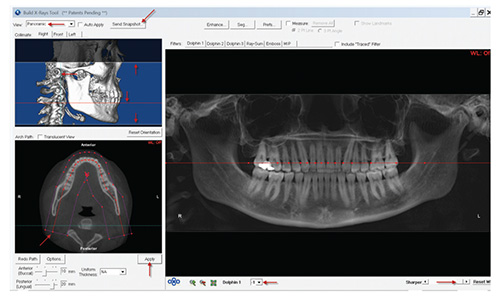

- Click "OK" to exit the "Sinus/Airway" window. Then

click "Build X-rays." Click "OK" in the pop-up window

that appears and the "Build X-rays Tool" window will

open. (See above.)

- Remain in the "Build X-rays Tool" window and select

"Panoramic" from the "View" drop-down menu. Adjust

the top white line to the bottom of the orbit, and the

bottom white line to below the chin. Adjust the blue line

to the left of the condyle and the red line to just below

the crown of the lower teeth.

Focus on the lower left side of the screen to create the

"Arch Path." Begin below the blue line on the left side

and click to place the first red path point. For optimal

visual quality, place two path points along the arch, then

click in the middle of every tooth to add path points.

Double click below the blue line on the right side to

complete the path. Then click "Apply." Adjust the

"Sharper" slider and the "Dolphin 1" Level to the doctor's

preference. Click "Send Snapshot" and "Save to

Dolphin Layout/Database."

- To save the panoramic X-ray image, click the square

indicated below (the "Image Title" will automatically

load with "X-ray Panoramic"). Then click "Save."